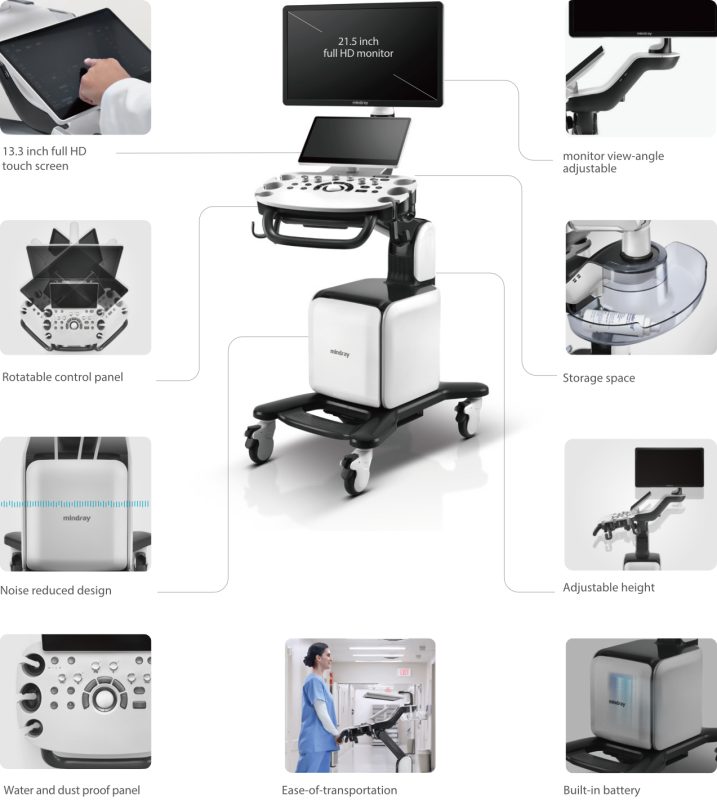

- 21.5″ Full HD LED monitor, height and side adjustable, automatic brightness correction

- 13.3″ control touch panel, foldable, gesture control

- adjustable control panel, very quiet operation

Ergonomic Design

Boosts daily work efficiency

- Bezel-less HD monitor for an immersive experience

- Full-HD touch screen with intuitive interaction

- Water and dustproof control panel for easy cleaning

- Built-in battery supports scan without AC power

- Magnetic front cover for simple cable management